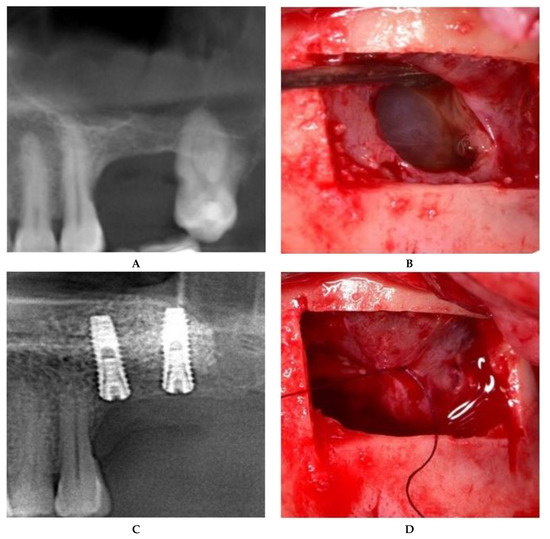

II.c. The treatment of maxillary sinus mucoceles requires deliberate incisions of the sinus membrane. The position and size of the incision were controlled by the surgeon, both to allow mucocele removal and to further seal off the Schneiderian membrane. The surgical approach to the incised Schneiderian membrane was suturing with an absorbable 6.0 suture with an 8-mm needle (SMI Company, Belgium). Fine-tipped needle holders (Devemed GmbH, Tutlingen, Germany) and anatomical tweezers were used to create three sutures, each with one double knot secured by two other simple knots (Figure 4).

Figure 4. Sinus floor augmentation simultaneous with mucocele removal. (A) Preoperative CBCT of the left maxillary sinus. (B) Mucocele pseudocyst visible through the incision. (C) Suture of the incised Schneiderian membrane. (D) Panoramic image after implant placement.